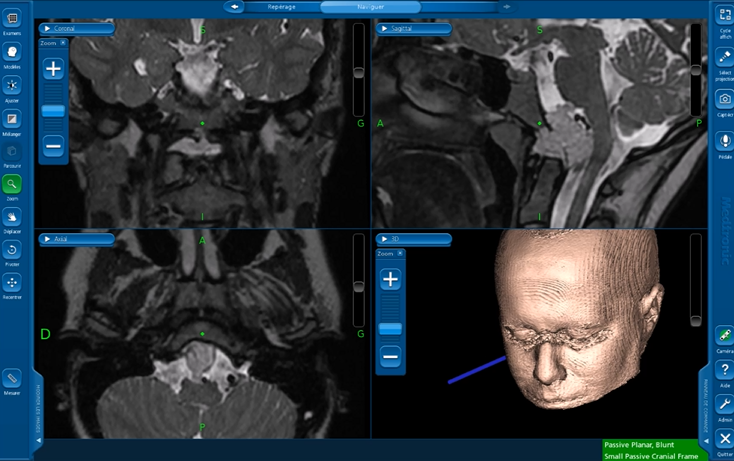

术前MRI

CT显示下斜坡和右侧枕骨髁部分损害

图1,术前和术后磁共振成像(MRI)。(A)术前矢状面t2加权MRI显示以颅颈交界区为中心的高信号病变(脊索瘤),伴有硬膜内延伸和神经血管结构受压。(B)术后矢状T2加权MRI显示肿瘤实现了全切。